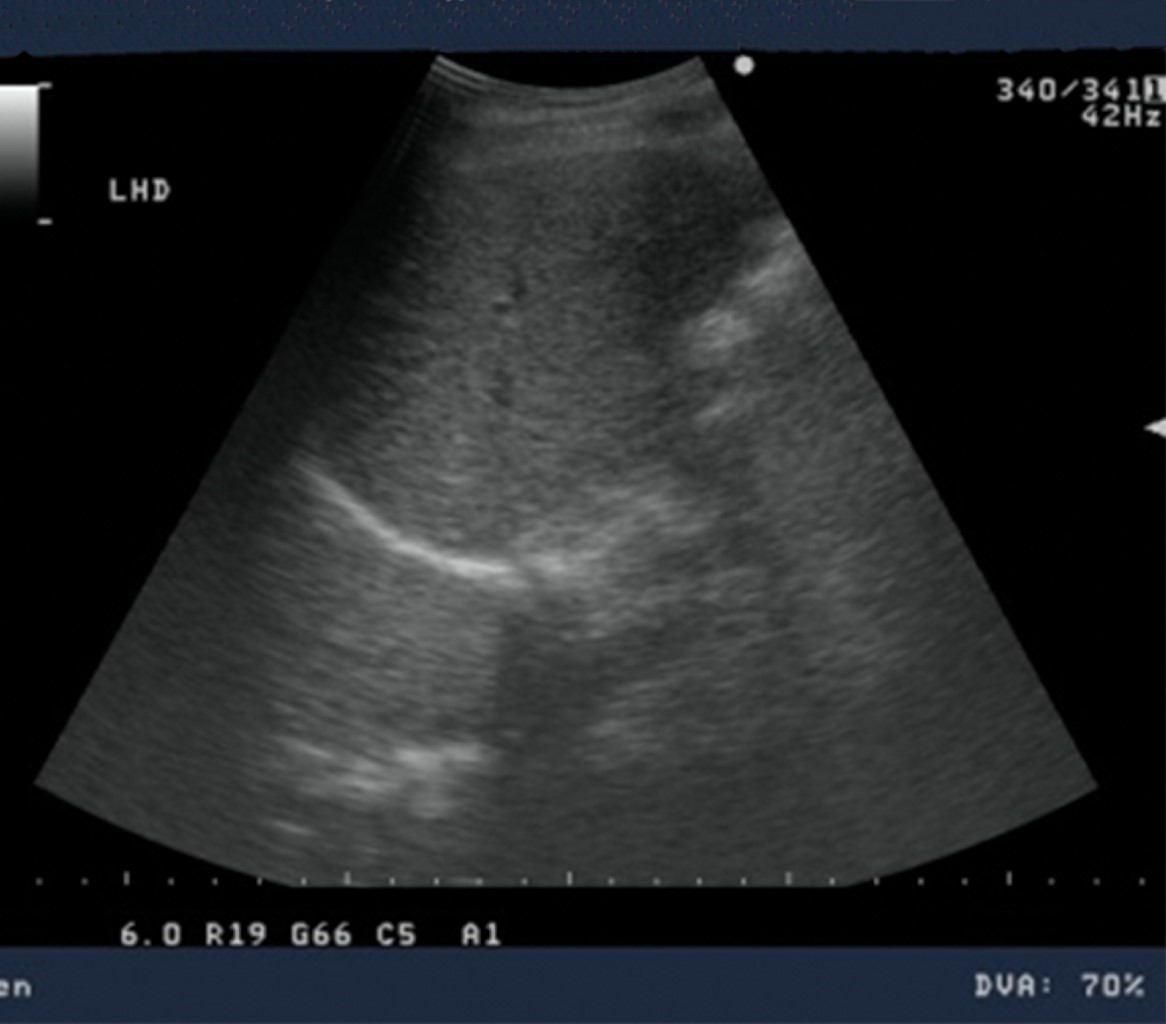

Se reinició la vía oral con dieta líquida y papillas retirándose paulatinamente la nutrición parenteral total y habiendo cedido la fiebre, mejorado su redistribución de líquidos corporales y los gastos de los drenajes hepáticos disminuido a menos de 40 cm3 en 24 horas, la paciente fue egresada a su domicilio el 20-11-2019 con cefalexina 500 mg c/6 horas, vía oral durante 15 días más y vigilancia de las pequeñas colecciones hepáticas remanentes con USG mensual durante tres meses en la consulta externa (Figura 7).